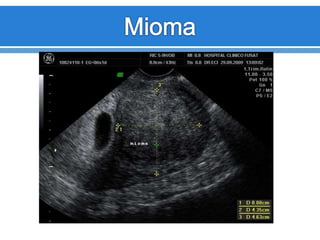

Leiomiomatosis

Los Leomiomas son

tumores benignos

formados por

músculo liso y tejido

conectivo.

Frecuencia de 20%

mujeres > 35 años

Son estrógeno

dependientes

Son múltiples o

únicos

Aspecto

variable.

Útero puede

estar

aumentado

de tamaño.

Hipoecogénicos.

Ecopatrón

Heterogéneo.

Atenuación

acústica o

sombra

acústica

posterior, sin

evidencia de

masa.

Anomalías del miometrio Leiomiomatosis Los Leomiomasson tumores benignos formados por músculo liso y tejido conectivo. Frecuencia de 20% mujeres > 35 años Son estrógeno dependientes Son múltiples o únicos